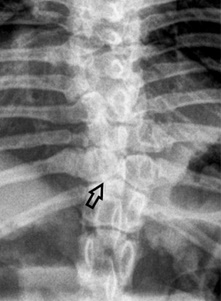

Χαρακτηρίζονται από συνδυασμένη απλασία της κοιλιακής και της μέσης μοίρας του σπονδυλικού σώματος με συνέπεια τη δημιουργία «σπονδύλου δίκην πεταλούδας». Οι σπόνδυλοι αυτοί απεικονίζονται σε ραχιαία προβολή.

Στην ακτινογραφία (ραχιαία προβολή) απεικονίζεται ο σπόνδυλος Θ12 που έχει το σχήμα πεταλούδας